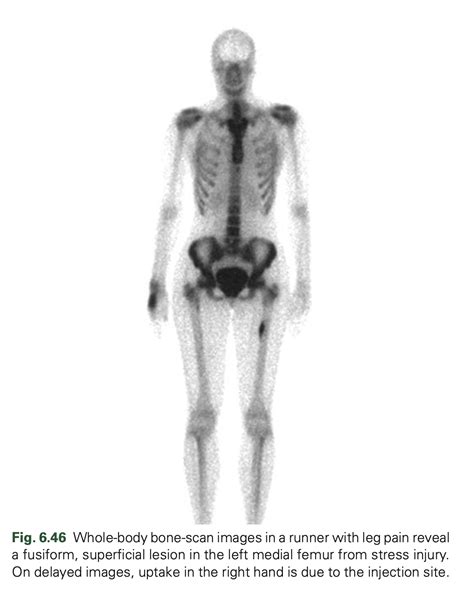

When you suspect you are dealing with a stress fracture, the first line of defense is the RICE method (Rest, Ice, Compression, Elevation). However, if your pain does not show significant improvement within one to two weeks of reduced activity, it is time to schedule a visit with an orthopedic specialist. A professional will often use imaging techniques like X-rays, MRIs, or bone scans to confirm the diagnosis. Because stress fractures are often hairline-thin, they may not show up on a standard X-ray in the early stages, which is why clinical judgment based on your reported symptoms is so important.